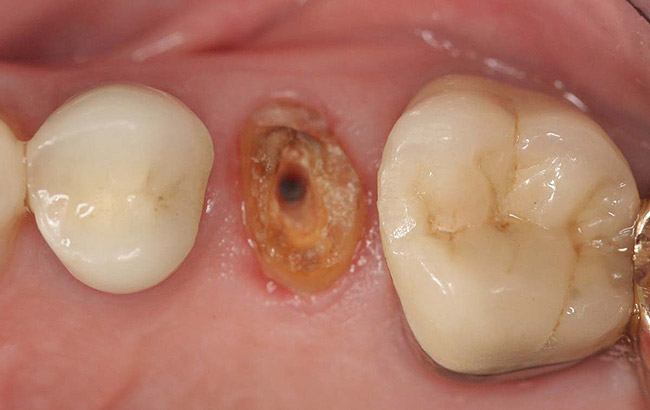

Figure 7  Second molar with the palatal canal prepared for post placement.

Figure 7